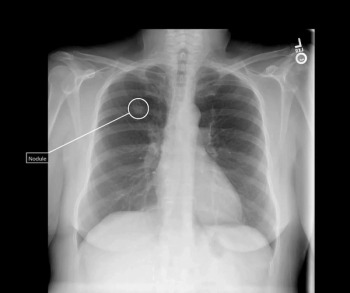

Tailored for incidental findings on chest radiographs, the qXR for Lung Nodule (qXR-LN) software utilizes artificial intelligence (AI) to help detect suspected pulmonary nodules ranging between 6 to 30 mm.